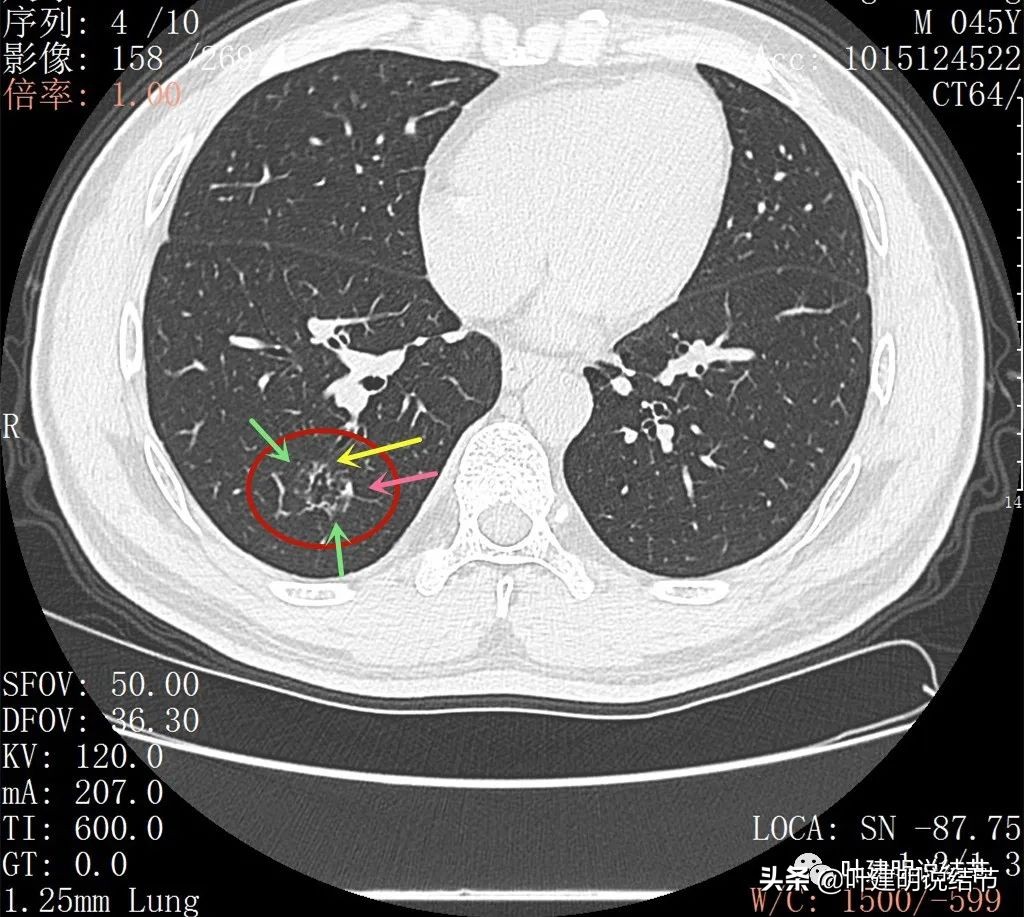

2022年2月平扫:

右下叶淡而散在的磨玻璃影

整体轮廓有点清楚,似见血管走行于病灶处

密度略不均